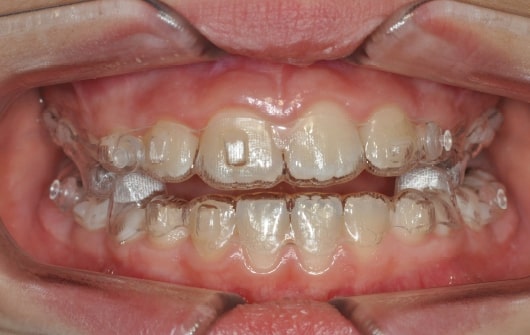

- Mandibular Advancement (A6 protocol) + angelBuon for Class 2 Elastics (Night Time)

Treatment details

AngelAligner KiD 1 (aligners changed every 10 days)

- Class 1 both sides

- Overjet/Overbite Correction

Treatment progress